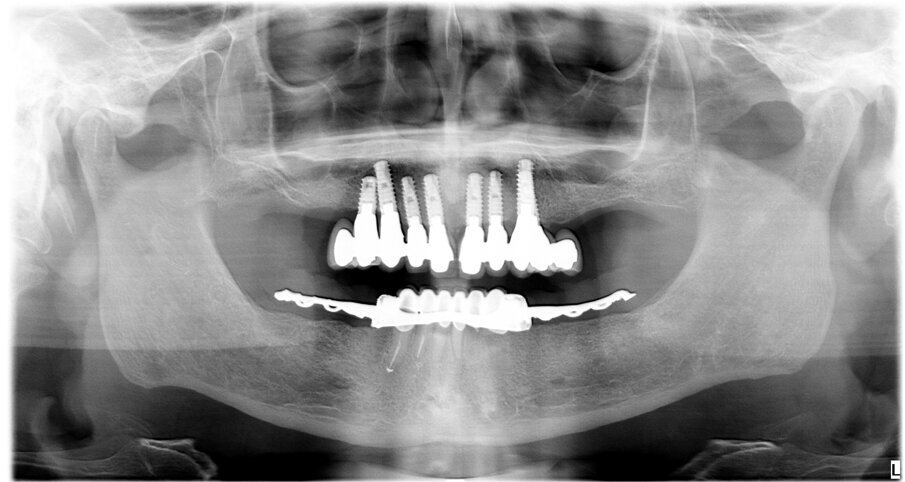

Paziente di sesso maschile di 73 anni, con anamnesi negativa per patologie di rilievo. All’esame clinico e radiografico si evidenzia nell’arcata inferiore la presenza di residui radicolari a supporto di un vecchio ponte, con attacchi per la stabilizzazione di una protesi scheletrata di tipo mobile. Prima di procedere alla fase chirurgica e di rimuovere lo scheletrito viene eseguita un impronta digitale con scanner (3Shape) in modo da registrare la dimensione verticale che verrà utilizzata come riferimento per la realizzazione del carico immediato. In sedazione cosciente e previa terapia antibiotica si procede alla rimozione dei residui radicolari, quindi si esegue una generosa osteotomia e si procede al posizionamento di numero 6 impianti assiali (AB Dental device) a esagono interno. Si esegue quindi la sutura dei lembi con vicryl 4/0 e si procede alla prese dell’impronta digitale utilizzando gli scan body come transfer (Figg. 1-11). I file in STL vengono inviati al laboratorio per la realizzazione della protesi provvisoria a carico immediato. Si applicano quindi le viti di guarigione. Dopo 72 ore si procede alla consegna del provvisorio che rimarrà in bocca per 4 mesi in attesa dell’osteointegrazione (Figg. 12-23).

Fig. 23 - Rx con carico immediato.